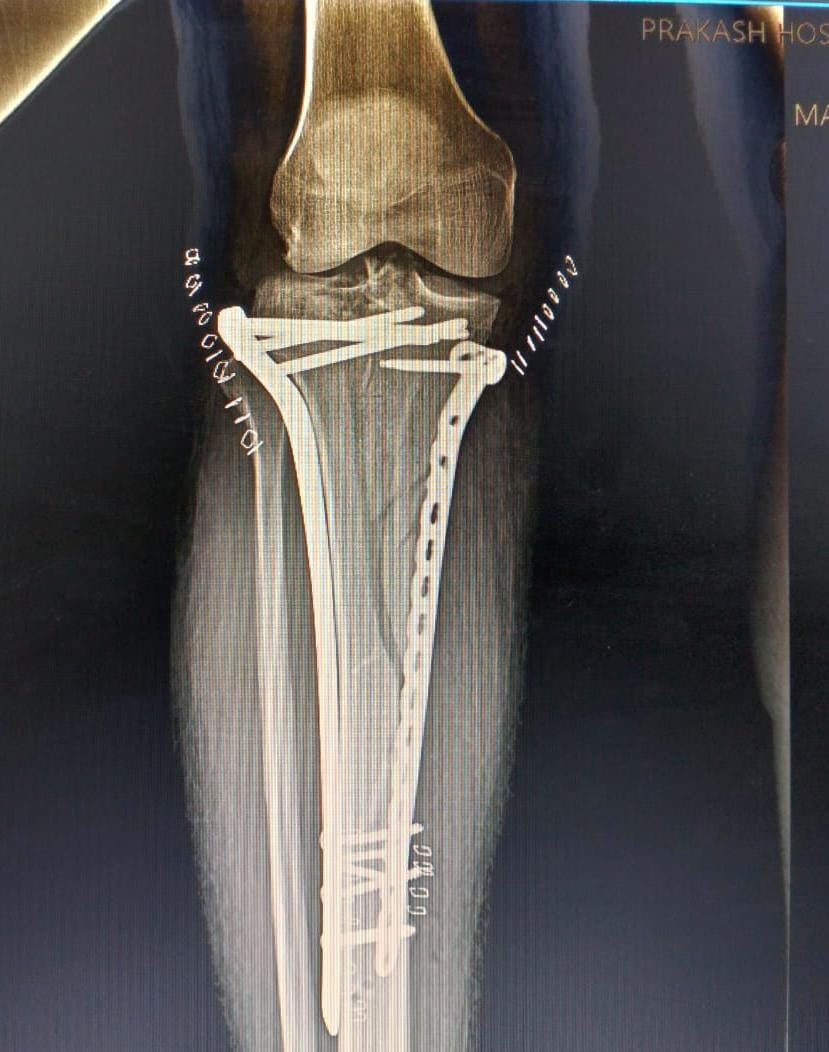

Knee replacement surgery is a procedure where damaged parts of the knee joint are replaced with artificial components to relieve pain and restore function.

Fracture surgery is a procedure to repair broken bones, ensuring proper alignment and stability for optimal healing.